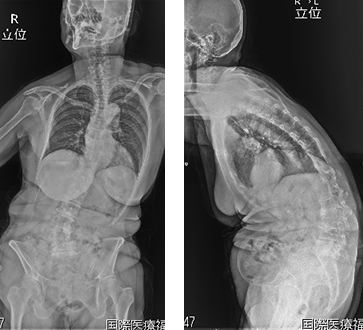

腰が曲がって前に重心があるため前かがみになってしまいます。

前と左に曲がって立位困難です。